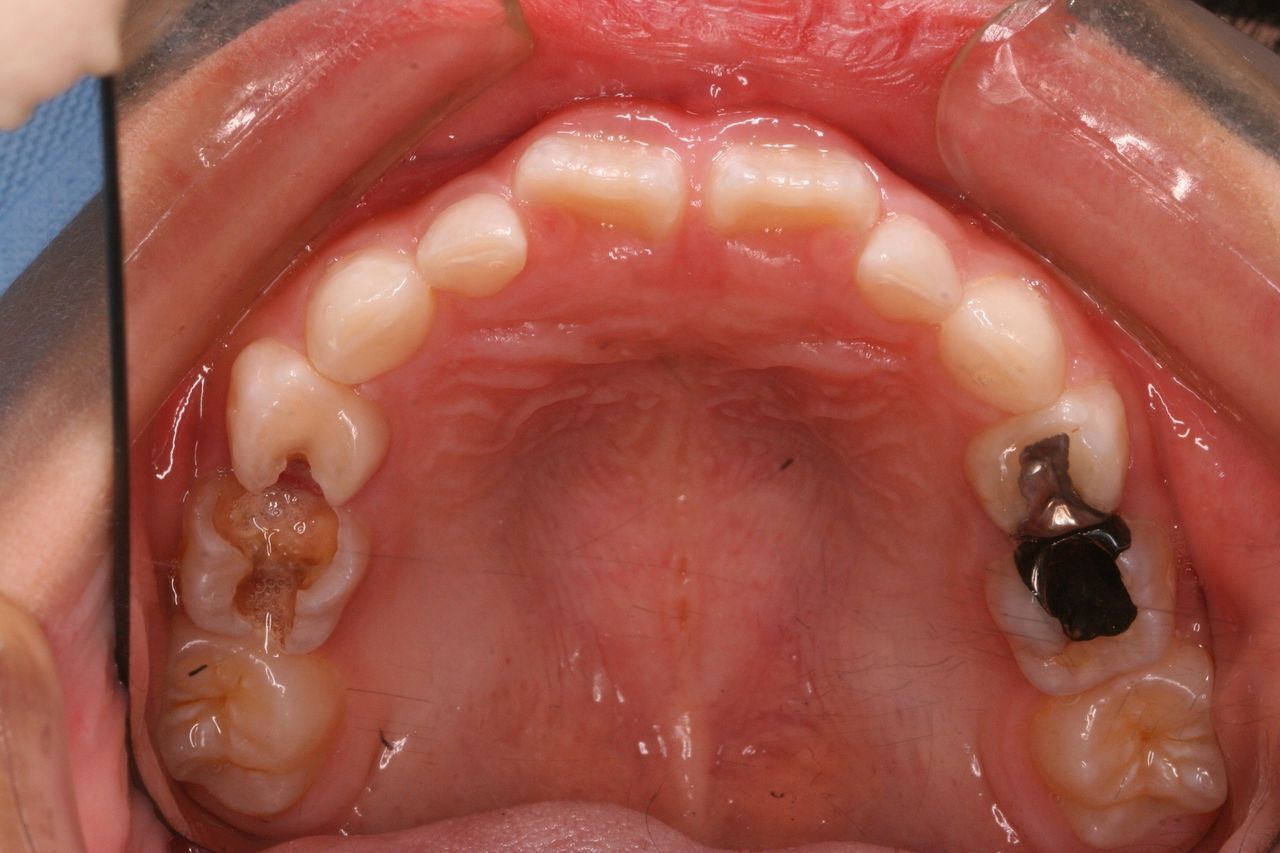

経過をみていくと、変な部分から大人の歯が生えてきました。

乳歯列時期に重篤な虫歯になった場合、あとから生えてくる永久歯は変な場所から生えてくることが多々あります。

理由は、乳歯が虫歯菌によって感染している状況下において、その上にある永久歯の卵はそのままの状況では自分も感染してしまいます。 まれに感染してしまった大人の歯は色が黒ずんだり、形がいびつな奇形的な歯になってしまいます。 多くの場合は感染した乳歯から離れていくのです。 つまり、永久歯の卵は避難しているわけです。

この状況をふりかえってみてもそうでした。

変なところから生えてきた永久歯を正常な方向に誘導するためには、その隣の乳歯も抜歯せざるを得ない状況になってしまいました。

また、一方でそうなると、反対側の乳歯の交換も促進していかなければ左右対称な歯列が完成しません。

この状況ではいくつかの乳歯をいっぺんに抜歯するといった処置をおこなう必要がありました。

横から生えてきた永久歯も向きは悪いですが、かなり良い方向に降りてきました。